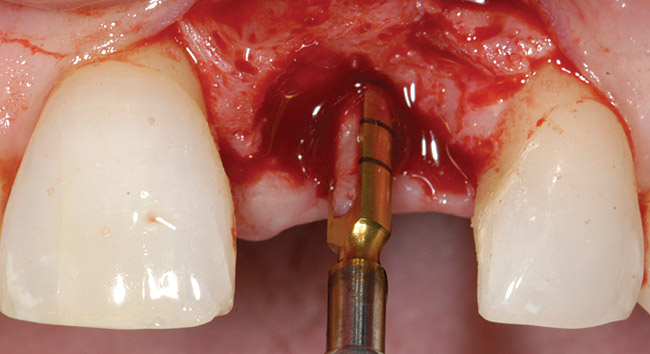

Treatment consisted of flapless extraction, socket grafting using mineralized bone allograft (Puros®, Zimmer Dental Inc, Carlsbad, CA), and a pedicled connective tissue graft36,37(Figure 11). Five months post-surgery, reentry was accomplished via a mid-crestal and labial sulcular incision. A crestal plasty was per- formed before implant placement into type II bone (Figure 12 and Figure 13). An immediate provisional was used for 3 months (Figure 14) before final crown fabrication (Figure 15).

Figure 13  Primary flap closure.

Figure 13